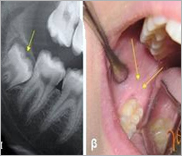

Εφαρμογές Laser

Χρησιμοποιούνται σε πάρα πολλούς τομείς της οδοντιατρικής, όπως η Ενδοδοντία (απονευρώσεις), η Περιοδοντολογία, η Αισθητική Οδοντιατρική